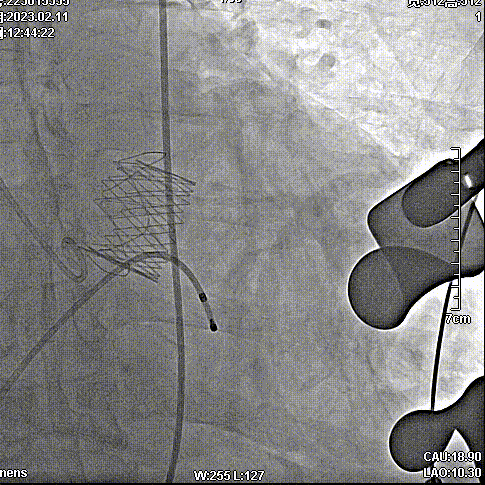

手术步骤

拔除股动脉血管鞘,缝合股动脉。手术顺利结束。